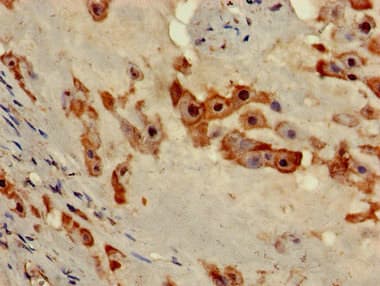

Rabbit Polyclonal NOB1 antibody. Suitable for WB, IHC-P, ICC/IF and reacts with Human, Mouse samples. Cited in 4 publications. Immunogen corresponding to Recombinant Fragment Protein within Human RNA-binding protein NOB1 aa 100-250.

Applications ICC/IF, IHC-P, WB